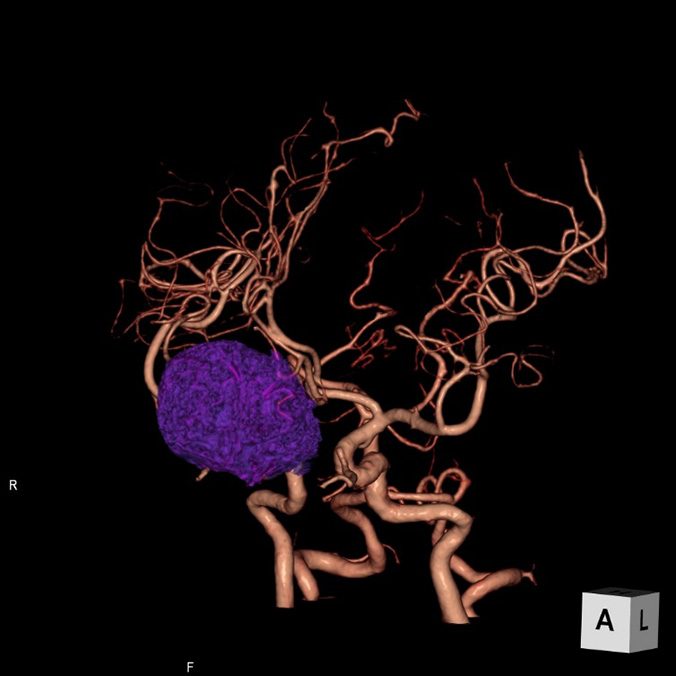

画像診断装置・放射線治療装置紹介

X線CT装置

64列 MDCT Aquilion CX (canon)

|

80列 MDCT Aquilion PRIME (canon)

80列 MDCT Aquilion PRIME SP(canon)

大きなトンネルの中に体を入れて、X線をあてて体の輪切りの写真を撮ります。CT検査には、単純CT検査と、造影剤を注射して撮影する造影CT検査があります。